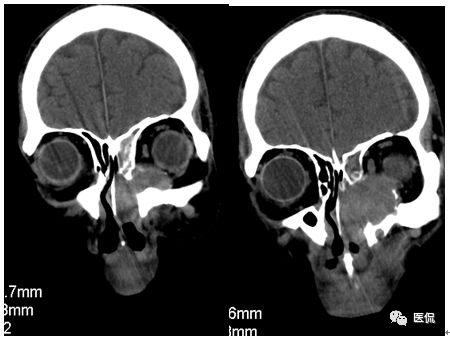

冠状位平扫

CT平扫及增强示:左侧上颌窦及鼻腔可见软组织密度影,呈膨胀性生长,周围骨质压迫性吸收破坏,累及左眶,病灶密度不均匀,周边区可见点状钙化,增动脉期轻度强化,局部见小灶性稍高密度区,静脉期病灶内见不均匀明显强化,CT值最高达117HU,延迟期强化范围有所增大。

本例病灶较大,周围骨质可见吸收破坏,并累及眼眶,病灶内少量钙化,增强扫描具有一定特征性,表现为动脉期轻度强化,局部见小灶性稍高密度区,静脉期病灶局部呈明显强化,CT值最高达117HU,延迟期强化范围有所增大,呈延迟渐进性强化的特点,推测为病灶内出血所致。